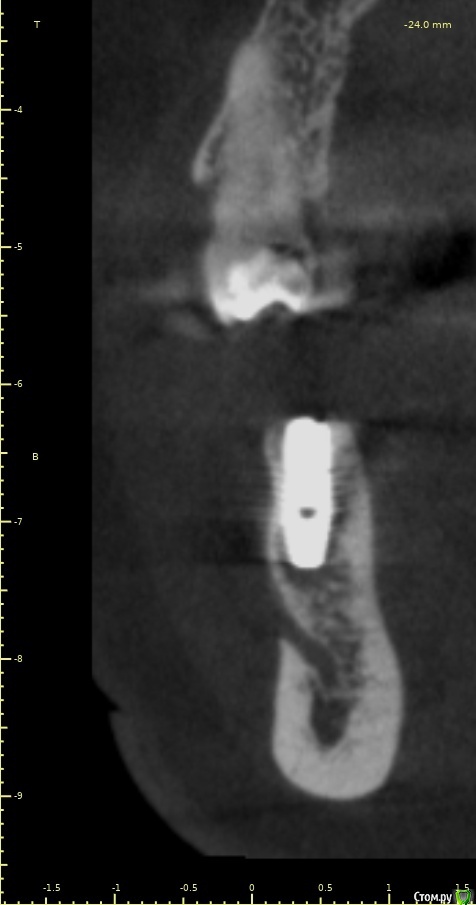

Женька Опубликовано 28 ноября, 2020 Поделиться Опубликовано 28 ноября, 2020 (изменено) Приветствую коллеги. В общем три недели назад 07.11.20 установил пациентке 2 имплантата в позиции 45-46. Гребень по ширине был около 6.5мм в области 4.5 и около 7.2мм в области 4.6 (с учётом заглубления на 1.5-2мм). Это была наверное первая имплантация во время которой я чувствовал себя спокойно и расслабленно. Всё прошло хорошо, немного покопался с непосредственным введением имплантатов, тк никак не хотели топиться на нужные 1.5мм. Поэтому пробовал методику с выкручиванием на пару витков и снова закручиванием. Особого толку не получил, потому взял финальную фрезу и чуть углублял ложе. Так несколько раз, тк боялся всё-таки немного что задену менталис и нлн. Ввиду того, что биотип у пациентки тончайший и язычно было совсем-совсем тонко - заглушки и швы. Назначил нпвс, ванны хг, аб терапию. Но на утро следующего дня пациентка сказала, что чувствует себя шикарно, решили что нпвс оставим, а аб терапию применять не будем (и грешу что в этом мою ошибка).Через неделю сняли швы, всё отлично.Спустя два дня после снятия начались какие-то "костные" боли, как говорит пациентка в области 4.5 импланта. Которые то отпускают, то снова наплывают. На 4.4 есть дефект твердых тканей (на фото виден), но судя по всему беспокоит не он .Пальпация вестибулярно в проекции 4.5 импланта болезненна, небольшая гиперемия, отёка нет. Гигиену пациентка запустила, тк боялась туда залезать и чистить. Снимки прилагаю первые два от 07.11, два последующих 28.11. Ну и внутри ротовые день операции и сегодняшние числа.Похоже 4.5 на выход? своими "туда-сюда" наверняка я нагрел всё что можно... снова расстройство в той работе, где накосячить предельно сложно... Добавка: пить аб ведь сейчас уже бесполезно? Изменено 28 ноября, 2020 пользователем Женька Ссылка на комментарий

Женька Опубликовано 14 декабря, 2020 Автор Поделиться Опубликовано 14 декабря, 2020 (изменено) Наконец-то получил КТ от пациентки...Боли значительно уменьшились, практически не беспокоит... Коллеги, что думаете? Я так понимаю это уже не фон от титана? и вердикт всё-таки один? Сам склоняюсь всё-таки более к понаблюдать. Вестибулярно конечно очень тонко Толщина была ~ 6.7мм Изменено 14 декабря, 2020 пользователем Женька Ссылка на комментарий

Irouil Опубликовано 14 декабря, 2020 Поделиться Опубликовано 14 декабря, 2020 Ну и где тут язычно передавленная кортикалка? Меня смущает только картина в области верхушки симптомного винта, ну и заглубление Я бы дождался уже срока интеграции Ссылка на комментарий

Женька Опубликовано 14 декабря, 2020 Автор Поделиться Опубликовано 14 декабря, 2020 Ну и где тут язычно передавленная кортикалка? Меня смущает только картина в области верхушки симптомного винта, ну и заглублениеНе знаю, я про язычную кортику не говорил. Меня тоже смущает... и в области соседа такого фона (а это не фон я уверен) нет... А с заглублением что не так? по прицелам там 1.5-2мм, на кт почему-то этих мм вообще нет и как будто крестально стоят Ссылка на комментарий